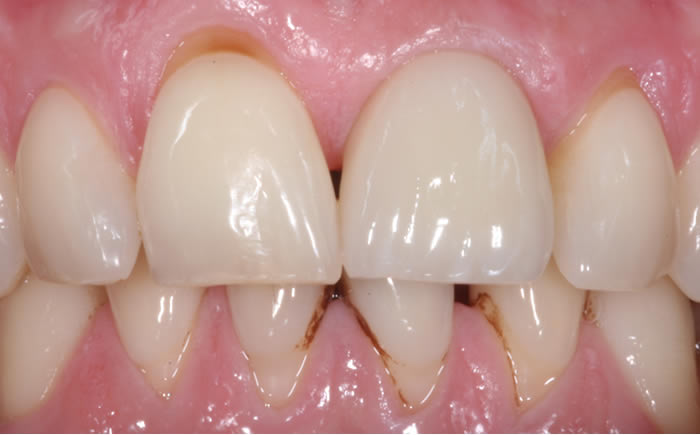

Before & After Gallery

More front teeth replaced by dental implants

Case Three (4 images)